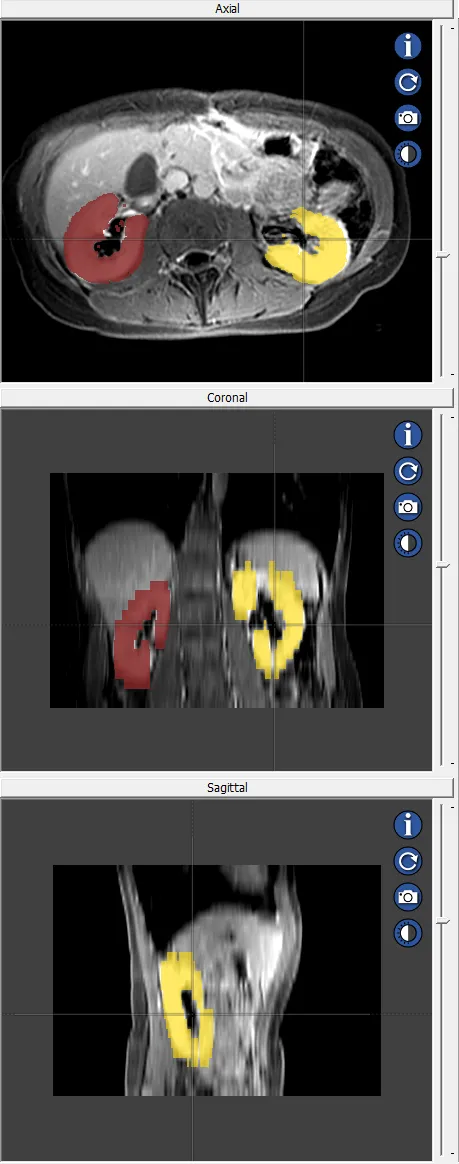

MRI segmentation of human brain ventricle

Quality assurance review of the AMOS 2022 Grand Challenge data